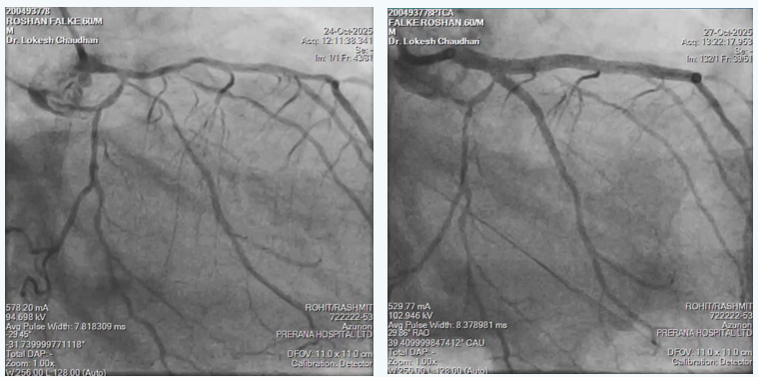

In view of multiple comorbidities and patients preference, high risk complex multi-vessel PCI (Including RCA-ISR-CTO & LM-LAD-LCX bifurcation) was planned and done as per plan under local anesthesia from right radial artery access as CT aerogram showed diffuse peripheral vascular disease starting from abdominal aorta extending into bilateral femoral arteries.

- Complex multi-vessel disease done through 6F Radial access

- RCA-ISR-CTO opened using CTO techniques via 6F catheter

- LM-LAD-LCX bifurcation done using modified MINI-CRUSH technique through 6F catheter

- Entire procedure was done with 140 ml of visipaque without causing any worsening of renal function.